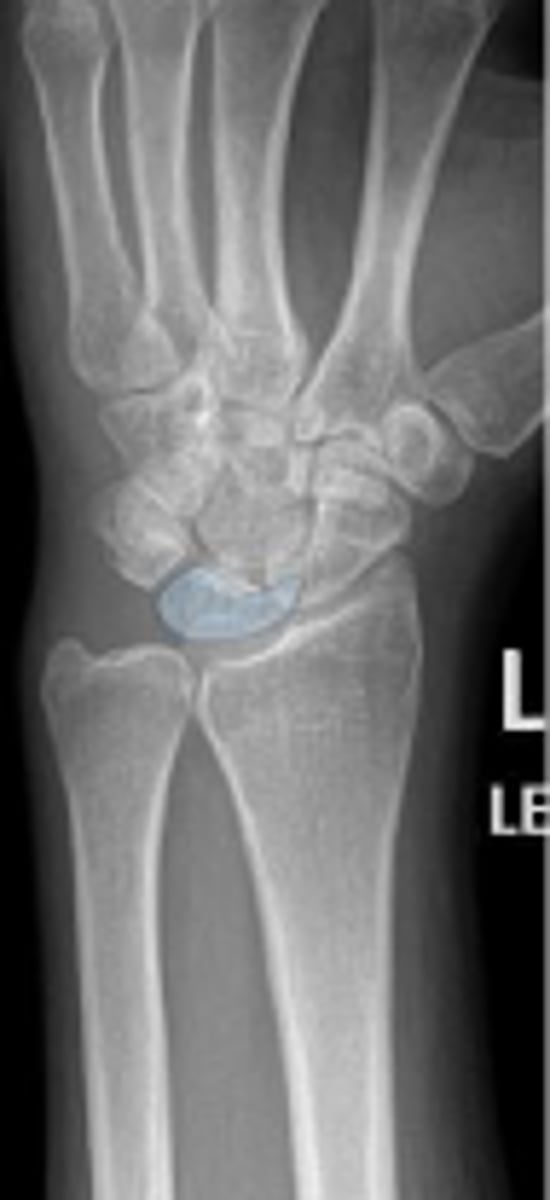

Medial oblique of the left wrist

What is the name of the radiographic view?

What is outlined?

Left scaphoid

Left lunate